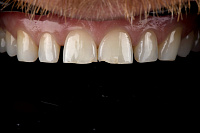

Наши работы